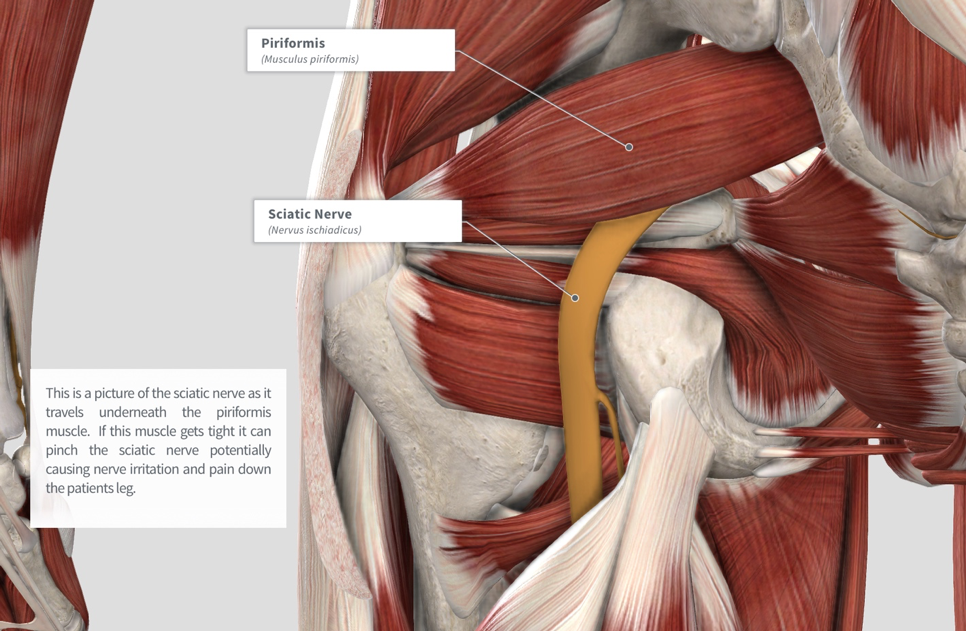

Анатомия мышц: Пириформис